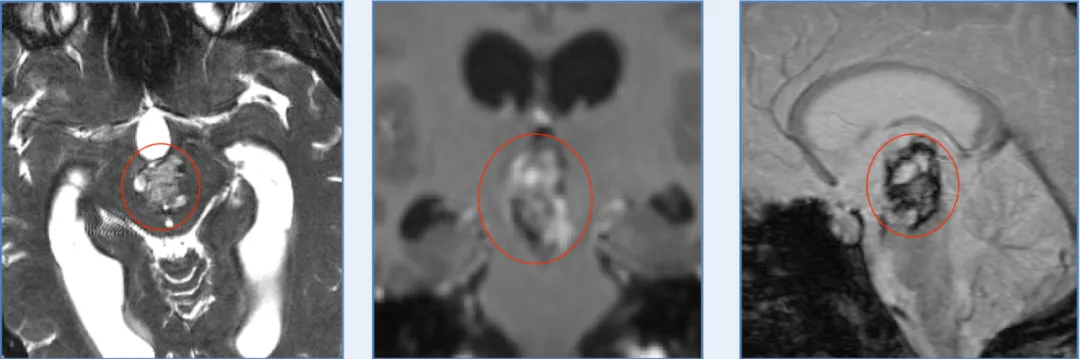

图:Luna的颅脑MR显示中脑巨大占位,混杂信号,海绵状血管瘤可能。